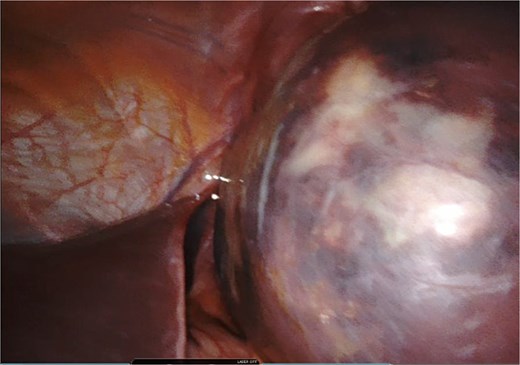

A giant splenic cyst was observed, compressing gastrointestinal organs, with limited mobilization (Fig. 3). Dissection of the splenoepiploic ligaments was performed using a bipolar energy device (Vessel Sealer), followed by dissection of the splenic flexure of the colon. The pre-splenic ligament was divided, and vascular control of the short gastric vessels was achieved. The vascular bed was identified with indocyanine green (ICG)-enhanced fluorescence (Fig. 4), and vascular control of the artery and vein was performed with a 40 mm stapler (Fig. 5). The splenophrenic ligament was divided, and the splenic bed was skeletonized (Fig. 6).

Intraoperative visualization of enlarged spleen and intraparenchymal cyst.

Use of ICG enhanced fluorescence for adequate visualization of splenic hilum.